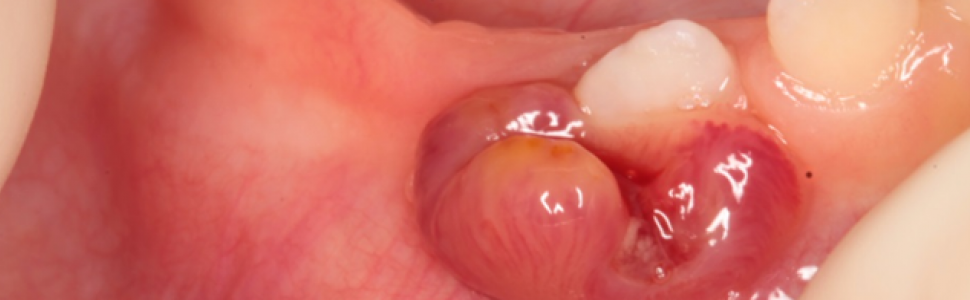

Opis przypadku: Obecnie 6-letniego pacjenta przyjęto w 11. miesiącu życia do Poradni Stomatologicznej dla Dzieci IPCZD ze zmianą na błonie śluzowej w okolicy zęba 83, która pojawiła się sześć tygodni wcześniej. Towarzyszyło jej obrzmienie oraz wyciek treści ropnej. Pacjent był konsultowany przez lekarzy dentystów, którzy dwukrotnie odbarczali zmianę oraz zlecili terapię antybiotykową, nie uzyskując znacznej poprawy. W momencie zgłoszenia się pacjenta do IPCZD w badaniu klinicznym stwierdzono w okolicy zęba 83 krwawiącą zmianę egzofityczną oraz rozdęcie części zębodołowej żuchwy w okolicy zębów 81-83. Węzły chłonne podżuchwowe były niepowiększone. W celu dalszej diagnostyki w znieczuleniu ogólnym wykonano tomografię komputerową (w obrazie uzyskując destrukcję kostną w trzonie żuchwy w okolicy zębów 82-83 z miejscowym rozdęciem) oraz biopsję zmiany. Na podstawie badań dodatkowych (HR-CT płuc, punkcja szpiku, scyntygrafia kości) oraz badania histopatologicznego rozpoznano histiocytozę z komórek Langerhansa – postać jednoogniskową kostną z zajęciem kości żuchwy po stronie prawej. Pacjenta zakwalifikowano do leczenia chemioterapią systemową oraz sterydoterapią: w fazie indukcji prednizonem i winblastyną (12 dawek przez 3 miesiące), następnie, w fazie leczenia podtrzymującego – winblastyną (3 dawki/1 miesiąc), do 12 miesięcy leczenia zgodnie z protokołem. Leczenie onkologiczne zakończono po roku od rozpoznania. Obecnie, po 5 latach od zakończenia leczenia, w kontrolnych badaniach TK nie stwierdzono wznowy procesu chorobowego.

Case reported: At present 6-year old patient reported at 11-month old to the pediatric dentistry clinic in The Children's Memorial Health Institute with a mucosal lesion in the area of the tooth 83, which appeared six weeks before. It was accompanied by swelling and pus leaking. The patient was consulted by dentists, who decompressed the lesion twice and prescribed antibiotic, without any prominent improvement. At the time of the examination in the Children` Memorial Health Institute exophytic, bleeding lesion next to the temporary right lower canine and distension of the body of the mandible in the area of teeth 81-83 were found. Submandibular lymph nodes weren`t enlarged. For further diagnosis in general anesthesia computed tomography was performed, revealing the image of bone destruction in the mandibular body in the area of teeth 82-83 with local distension, and biopsy of the lesion. Based on additional examinations (lungs HR CT, bone marrow aspiration, bone scintigraphy) and histopathological examination Langerhans cell histiocytosis – unifocal form in the body of the mandible on the right side was diagnosed. The patient was qualified for systemic chemiotherapy and steroid therapy: induction phase prednisone and 12 doses of vinblastine by 3 months, followed by maintenance chemotherapy of vinblastine to 12 months of treatment. Oncologic treatment was finished after one year from diagnosis. Currently 5 years after treatment termination, in control computed tomographies, recurrence of the disease is not observed.